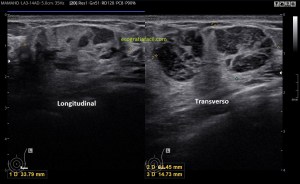

Con la eco pasa igual…cuando queremos estudiar, por ejemplo, el recto anterior del muslo en axial,perfecto…pero en longitudinal, como la imagen 2, se complica porque desde la rótula a la inserción en la cadera, tenemos mucho recorrido. En este caso hacemos lo mismo que cuando hacemos la foto del atardecer…nos ponemos en un extremo, activamos la funciona, recorremos suave y continuamente por la anatomía que queremos fotografiar y ya está…mira la pantalla y no el movimiento de tu mano,como si hicieses la foto, ves la pantalla,pero no como mueves el teléfono.

Es muy útil para lesiones que han crecido mucho y no podemos conjugar en una sola imagen, por ejemplo, un lipoma, cuando superan la medida de la huella de la sonda no son medibles, hay que usar «panoramic view», y como este caso, otros muchos.